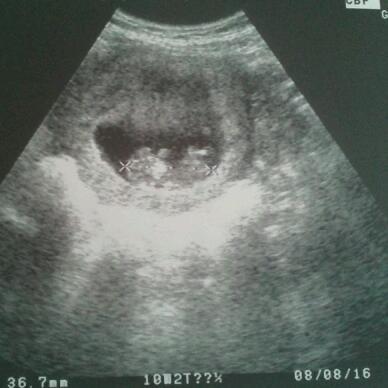

Alles super. Baby hat gewunken und war wie verrückt am hüpfen 37mm groß.

Bild zu Gestern Frauenarzt Termin gehabt - Schwanger - wer noch? Rund um die Schwangerschaft

Datum 08/08/2015 ????

Es steht da 8.8.2016 und nicht 2015.

Wir haben ja erst Januar 2016. Ist wirklich etwas verwirrend oder ist das dein Entbindungstermin? Lg

Das wird der ET sein. Und es steht nun wirklich unverkennbar 2016 und nicht 2015 drauf. Ansonsten würde ich wohl eine Brille empfehlen

Also normaler weise habe ich am 9.8 ET aber das Baby ist ein bisschen größer vielleicht dann doch 8.8 wird.